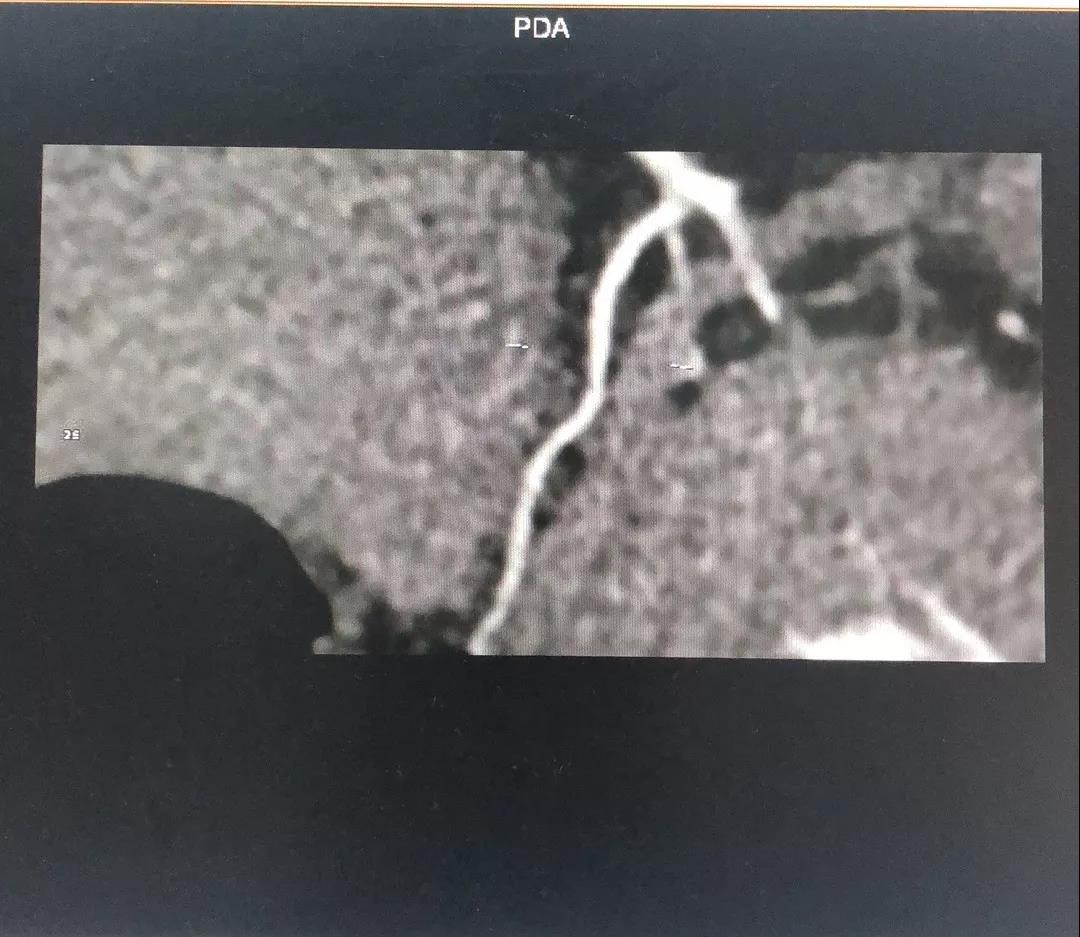

关于RCA

RCA CTA特点

1、入口清楚;

2、闭塞段长度小于20cm;

3、闭塞段血管无明显扭曲;

4、闭塞段内有两处明显的钙化斑块;

5、闭塞出口处血管相对比较“健康”;

6、侧枝血管汇入左室后支;

7、后三叉处的血管相对比较“健康”。